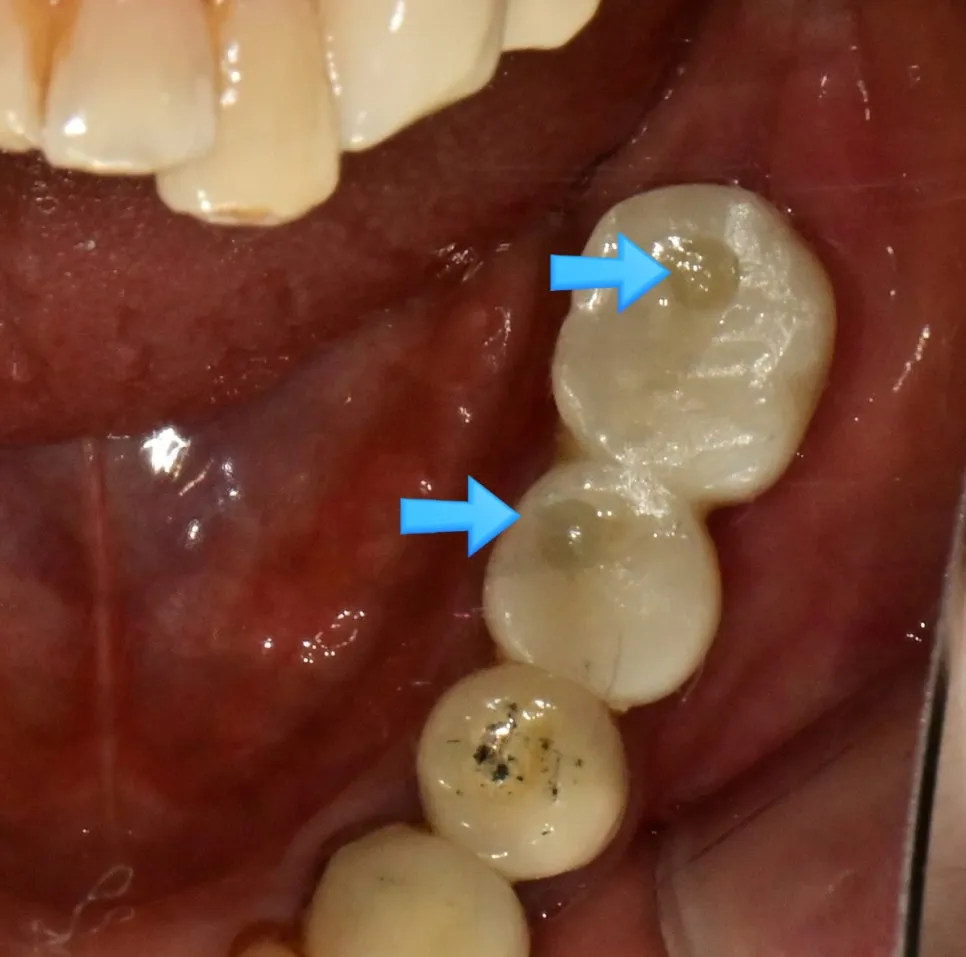

SCRP 보철물 최종 장착 — 파란색 화살표가 나사 접근 구멍(Access Hole)을 가리킵니다

수술 후 보철물을 장착해 드리면, “원장님, 치아 씹는 면에 왜 구멍이 있나요?”라고 물어보시는 분들이 계신데요.

이는 SCRP(Screw-Cement Retained Prosthesis, 나사-시멘트 유지형 보철물) 타입의 보철물로, 나사(Screw)를 이용해 임플란트와 보철물을 연결하는 방식입니다.

1. 접착제(Cement) 완전 제거 가능

임플란트 보철물의 가장 큰 고민은 “접착제를 완전히 제거했는가?”입니다! 임플란트 머리 위에 나사에 접근할 수 있는 형태를 만들면, 접착제를 완전히 제거할 수 있습니다. 남아 있는 잔여 접착제는 임플란트 주위염의 원인이 될 수 있기 때문에 이 부분이 매우 중요합니다.

2. 분리·세척·수리 용이

사용하시다가 임플란트 주변 잇몸이 붓거나 음식물이 끼어 청소가 필요할 때, 혹은 나사가 풀렸을 때 보철물을 뜯어내지 않고 나사만 풀어 분리 후 세척 및 수리가 가능합니다.

보철물에 남아 있는 접착제(Cement) — 깨끗한 제거가 임플란트 건강의 핵심

나사 구멍(Access Hole)이 있는 것은 결함이 아니라, 문제가 생겼을 때 쉽게 대처하기 위한 가장 좋은 진료 방식입니다!

(구멍은 평소에는 레진 등으로 메워두니 걱정하지 않으셔도 됩니다!!)